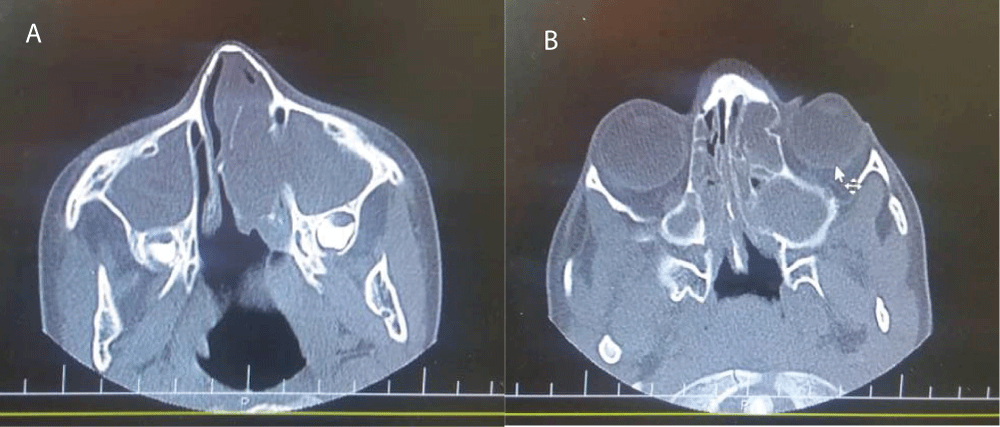

In laboratory studies, normal amounts of serum electrolytes was detected and chloride tests were in borderline and normal ranges (53 mmol/lit and 36 mmol/lit). Stool test for fat drop was negative. Blood gases analysis and O2 saturation were normal. There was no problem in Immunological workup including immunoglobulins levels, IgG subclasses, antibody responses to vaccines and flow cytometery. Saccharin blue test was done to evaluation of cilliary dyskinesia and the result was normal. In imaging studies, computed tomography (CT) scan revealed normal chest but congestion in maxillary and ethmoidal sinuses accompany with bone attenuation and remodeling in paranasal sinuses (Figure 1A,B). Due to strong suspicion of CF, CFTR study was carried out and was found to have C 3717+ 12191C>T homozygous that is a class V mutation.

Figure 1: A, B: Paranasal sinuses computed tomography scan show congestion in maxillary and ethmoidal sinuses accompany with bone attenuation and remodeling in paranasal sinuses.